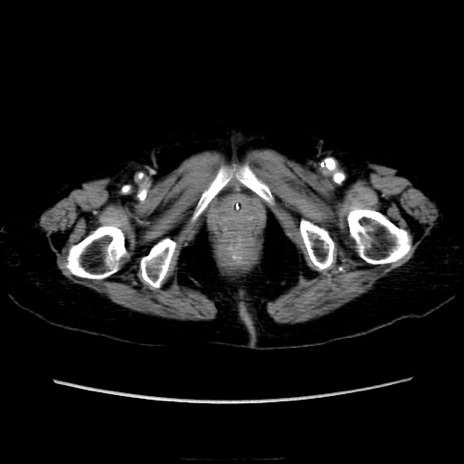

症例40(横断像)

【症例】90歳代女性

【主訴】腹痛・嘔吐

【現病歴】 食欲低下、嘔吐があり昨日他院受診。肺炎と診断され入院となる。入院後より腹部全体に圧痛あり。胃管留置され経過みていたが、症状持続するため、

当院転院となる。

【既往歴】胸椎圧迫骨折、胆石症

【身体所見】腹部:中央に激痛あり、圧痛あり、反跳痛不明

【データ】WBC 17100、CRP 18.82

横断像